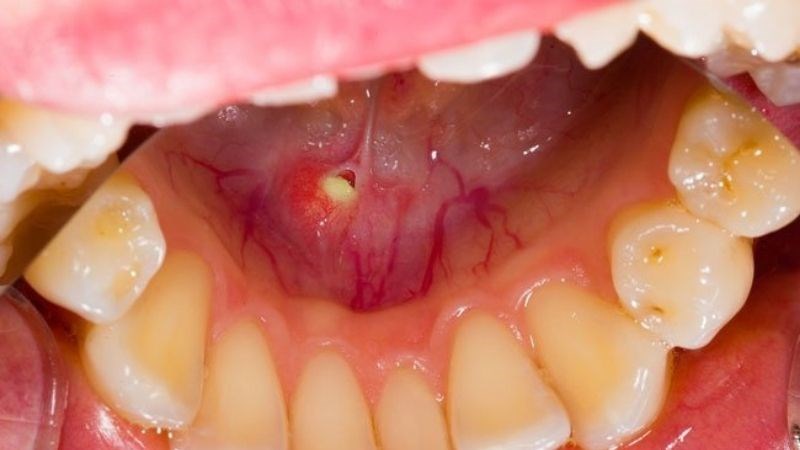

Sỏi tuyến nước bọt là tình trạng xuất hiện sỏi trong tuyến nước bọt hoặc ống (ống dẫn) tuyến nước bọt. Chính những điều này làm cản trở sự di chuyển của nước bọt trong tuyến.

Sỏi tuyến nước bọt thường xuất hiện ở tuyến dưới hàm. Trong một số ít trường hợp, nó có thể xuất hiện ở nhiều tuyến nước bọt khác nhau.

Sỏi tuyến nước bọt là những chất tích tụ và lắng đọng trong tuyến nước bọt